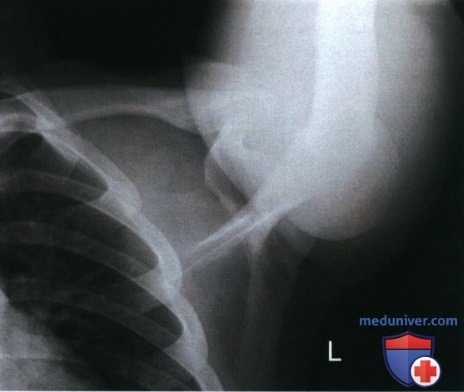

Рекомендации по анализу рентгенограмм (рис. 1):

РИСУНОК 1 Рентгенограмма ключицы в ПЗ проекции: правильное положение.

• Медиальный конец ключицы находится вблизи латерального края позвоночного столба (рис. 3 и 4)

• Ключица и верхний угол лопатки визуализируются на одном поперечном уровне (рис. 5 и 6)

РИСУНОК 3 Рентгенограмма ключицы в ПЗ проекции. Пациент повернут в противоположную сторону от исследуемой ключицы. РИСУНОК 4 Рентгенограмма ключицы в ПЗ проекции. Пациент повернут в сторону исследуемой ключицы. РИСУНОК 5 Рентгенограмма ключицы в ПЗ проекции. Верх срединной коронарной плоскости наклонен вперед. РИСУНОК 6 Рентгенограмма ключицы в ПЗ проекции. Верх срединной коронарной плоскости наклонен назад.

а) Поворот туловища в противоположную сторону от исследуемой ключицы. На рентгенограмме ключицы в ПЗ проекции выявить ее ротацию и продольное проекционное укорочение можно, сравнив положение медиального конца ключицы и позвоночного столба. Если туловище отвернуто от исследуемой ключицы, то ее медиальный конец будет накладываться на позвоночный столб (рис. 3).

б) Поворот туловища в сторону исследуемой ключицы. Если при рентгенографии ключицы в ПЗ проекции туловище повернуто к исследуемой ключице, на рентгенограмме медиальный конец ключицы будет отодвинут от позвоночного столба, а сама она будет подвергаться продольному проекционному укорочению (рис. 4).

в) Наклон верха срединной коронарной плоскости вперед. Если при рентгенографии ключицы в ПЗ проекции верх срединной коронарной плоскости наклонен вперед, на рентгенограмме верхний угол лопатки будет визуализироваться выше ключицы (рис. 4).

г) Наклон верха срединной коронарной плоскости назад. Если при рентгенографии ключицы в ПЗ проекции верх срединной коронарной плоскости наклонен назад, на рентгенограмме верхний угол лопатки будет визуализироваться ниже ключицы (рис. 5).